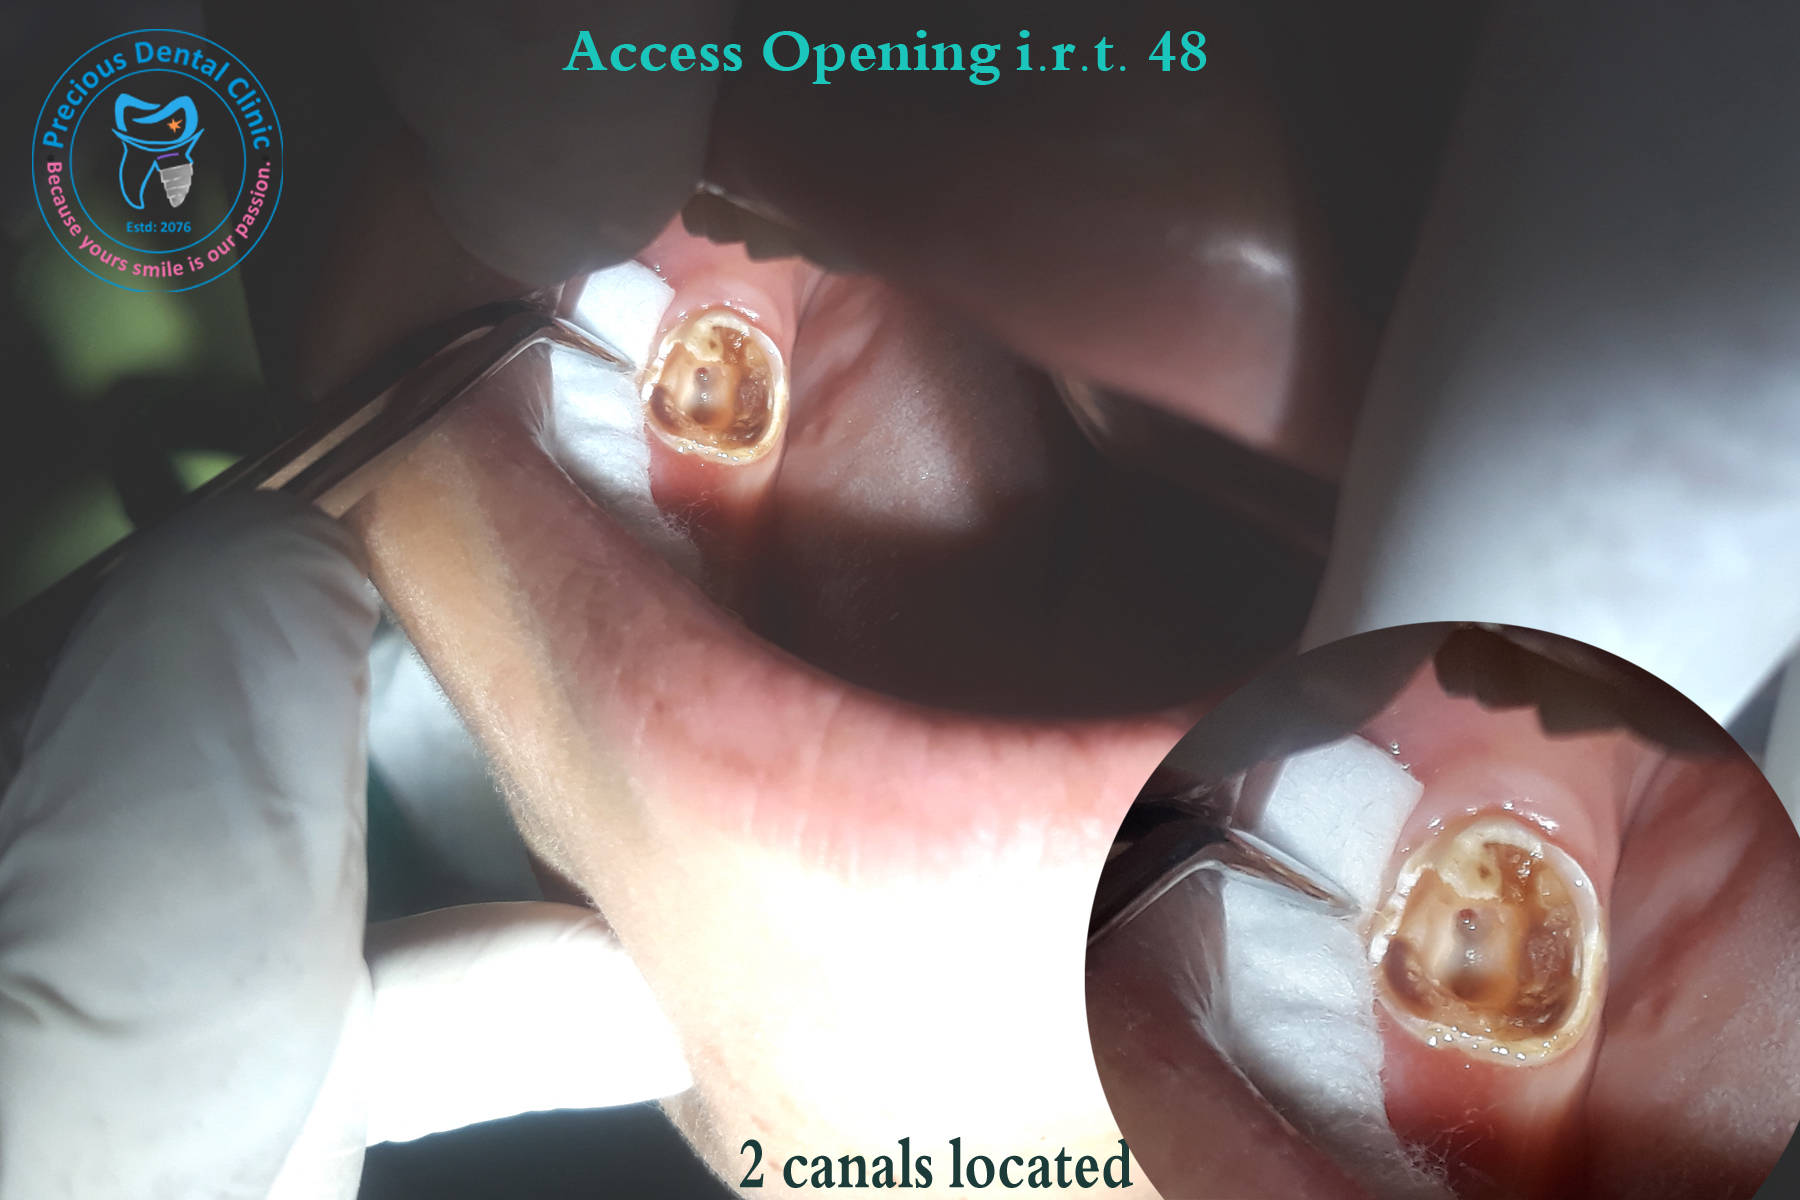

Root Carries AO with Canals

AO with Canals Incisal Fracture & Crack